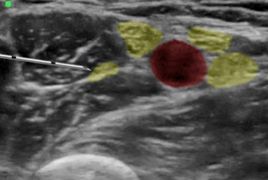

Ultraschallgesteuerte Gefäßzugänge und Regionalanästhesie (USGRA)

Moderne Ultraschallsysteme ermöglichen es uns die gesamte Palette der ultraschall-gesteuerten Gefäßzugänge und Regionalanästhesien aller Altersgruppen vom Säugling bis zum alten Menschen durchzuführen.